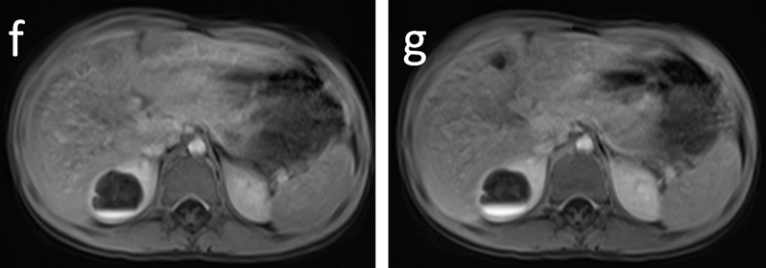

3、磁共振主要表现为:T2 高信号,可以看到细小的裂隙与肾盏相通,在 MRU 上更为清晰;

磁共振增强上可以看到造影剂进入囊腔内;